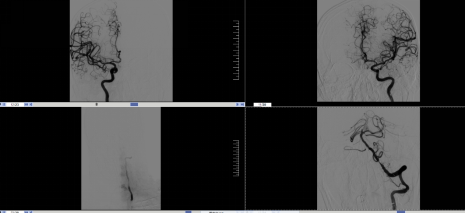

图1 磁共振显示DWI与T2 Flair序列不匹配

急查头颅磁共振显示:脑干小脑多发急性脑梗死,基底动脉闭塞。该患者DWI-T2FLAIR序列不匹配,符合静脉溶栓指征,积极与病人家属沟通后,行静脉溶栓。静脉溶栓后患者症状无明显改善,下一步怎么办?患者还正值壮年,如果就这样保守治疗预后较差,患者可能丧失劳动能力!跟我的上级医生黄圣明老师汇报情况后,决定进一步桥接介入治疗,遂联合介入科刘要先主任急诊为患者行“脑血管造影+经皮颅内动脉取栓术”,取栓术中可见患者闭塞的基底动脉再通,血供恢复。术后送ICU观察。